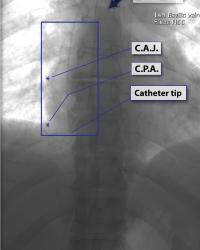

Often, the cavo-atrial junction can be approximated accurately as about 5 cm below the carina |

|